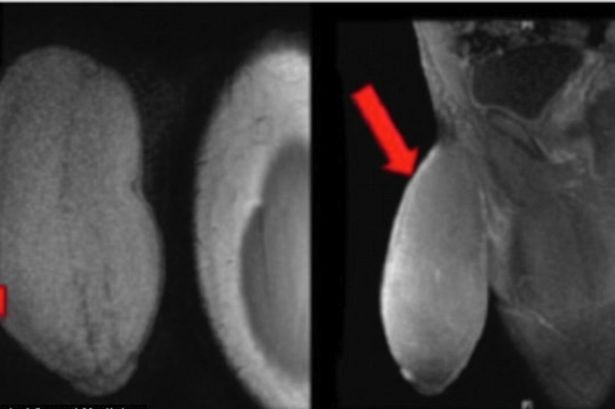

영국 일간지 ‘미러’는 13일(이하 한국시간) 성기 축소 수술을 받은 17세 소년에 대해 보도했다. 이 매체에 따르면 이 남성의 성기는 7인치에 달한 것으로 알려졌다. 하지만 둘레 역시 10인치로 ‘럭비공’ 모양의 성기를 가져 생활에 불편을 겪었다.

영국 '미러' 홈페이지 캡처.